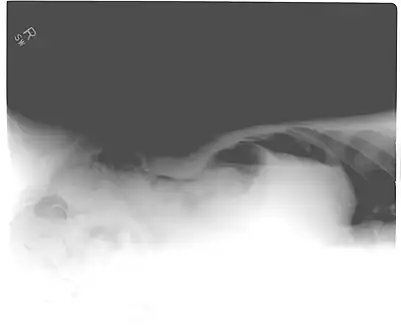

Pneumoperitoneum seen on X-ray with the patient lying on his left side.

When present, pneumoperitoneum can be seen on projectional radiography, but small amounts are often missed, and CT scan is nowadays regarded as a criterion standard in the assessment of a pneumoperitoneum.[18] CT can visualize quantities as small as 5 cm3 of air or gas.

Signs that can be seen on projectional radiography are shown below: